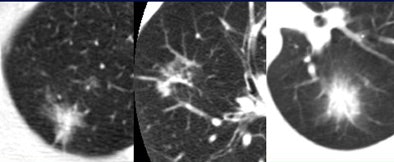

| Three focal ground-glass opacities (GGO) show the variety of presentations at MDCT. The lesion at left has a hazy appearance, with uniform surface lucency. The nodule in the center image is more subtle; no architectural distortion can be seen in the surrounding parenchyma. The GGO at right is rounder and smaller. All images courtesy of Dr. Ella Kazerooni. |